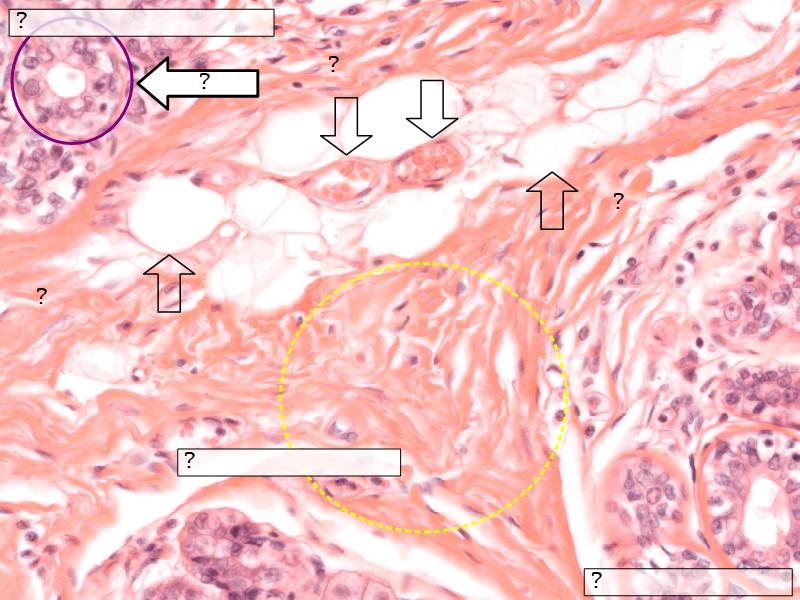

Alveolar cells

- Apocrine secretion

- Active state

- Resting state

Morphology

What are the main morphological features of the nipple?

(4)

Morphology

- Covered with skin

- Consists of dense collagenous connective tissue

- Interlaced with smooth muscle fibres

- Contains openings of lactiferous ducts

Skin

- Keratinized stratified squamous epithelium

- Sebaceous glands

Stroma

- Collagenous connective tissue

- Irregular dense connective tissue

- Smooth muscle

- Fibres and bundles

- Lactiferous sinusses

- Stratified cuboidal epithelium